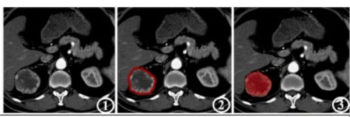

In comparison to a model based on clinicopathological risk factors, a CT radiomics-based machine learning model offered greater than a 10 percent higher AUC for predicting five-year recurrence-free survival in patients with non-metastatic clear cell renal cell carcinoma (ccRCC).